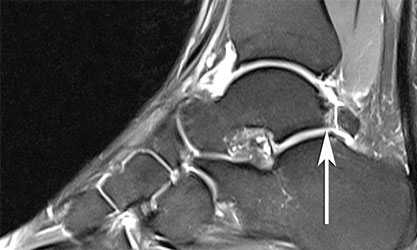

МРТ для диагностики недуга не является обязательным исследованием. Его выполнение рекомендуется, если необходимо провести дифференциальную диагностику с другими патологиями либо в начальных стадиях патологии.

Задний импиджмент синдром

И наоборот, при заднем импинджмент-синдроме снижена амплитуда сгибания стопы с выраженной болью в задних отделах сустава в положении крайнего сгибания стопы. Стресс-тест заключается в том, чтобы пациент встал на носочки. В этом положении возникает резкая боль в задних отделах голеностопного сустава.

Рентгенограммы пациента с задним импиджмент синдромом

ЗАДНИЙ ИМПИНДЖМЕНТ ГОЛЕНОСТОПНОГО СУСТАВА

Задний импинджмент голеностопного сустава это болевой синдром, при котором пациент испытывает болевые ощущения в заднем отделе стопы в положении подошвенного сгибания голеностопного сустава.

ЧТО ЭТО ТАКОЕ

Задний импинджмент голеностопного сустава - болевой синдром, при котором пациент испытывает болевые ощущения в заднем отделе стопы, в основном в положении подошвенного сгибания голеностопного сустава. Синдром может стать следствием как острой, так и хронической травмы. Нередко это состояние связано с наличием такой особенности анатомии, как os trigonum - добавочная косточка в голеностопном суставе.

ДИАГНОСТИКА ЗАДНЕГО ИМПИНДЖМЕНТА

Диагностика проводится на основании данных анамнеза, непосредственно осмотра врачом и рентгенологического исследования.

В ходе обследования обычно выявляется боль при ощупывании в области заднего отдела таранной кости.

Также проводится серия специальных провокационных тестов, которые заключается в проведении быстрых подошвенных сгибаний голеностопного сустава, выполняемых в различных положениях стопы. При положительных результатах тестов в сочетании с болью при ощупывании может быть показана диагностическая блокада сустава раствором местного анестетика.

Лучевая диагностика

На рентгенограмме нередко можно увидеть гипертрофированный задний отросток таранной кости или os trigonum. В случаях перенесенных ранее травм мы ищем признаки несросшегося перелома в этой области.